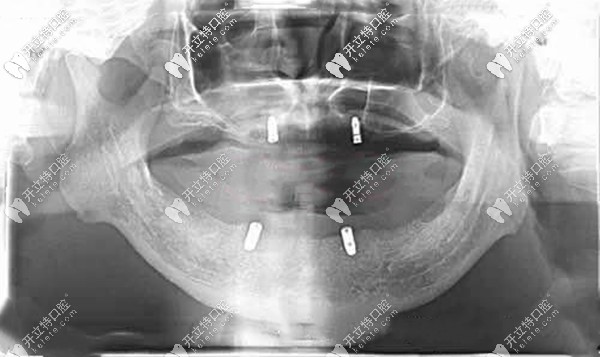

全口無牙頜種植覆蓋義齒后的CT片▼

Locator全口種植覆蓋義齒的優(yōu)缺點(diǎn)